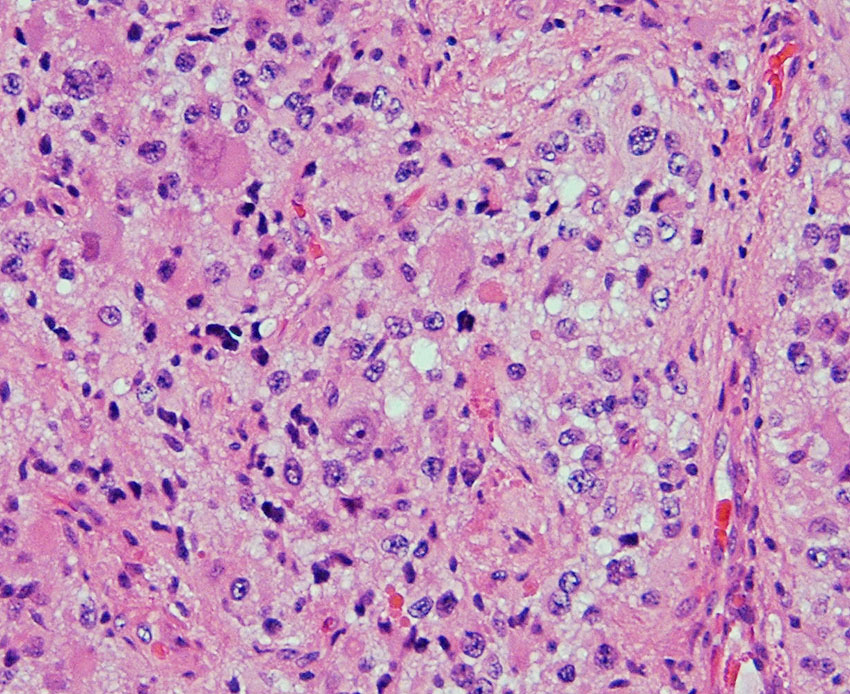

7才の時に音読でつかえるようになり,眼で何かを追っているような欠伸発作(左側頭葉てんかん)を繰り返すようになり,強直間代発作を生じて腫瘍が発見されました。下側頭回底面の皮質に発生した境界明瞭な腫瘍であり,周囲に脳浮腫を伴っています。T2強調画像で線維成分の多い硬い部分は低信号に,軟らかい部分はやや高信号となり,ガドリニウムでheterogenousに増強されます。グレード1の神経節膠腫としては非典型的な画像所見で術前診断は難しいもので,PXA pleomorphic xanthoastrocytoma も疑いました。もちろん治療としては開頭手術での全摘出です。術後に発作は消失しています。

構成要素はGFAP陽性の膠細胞が多く認められます。神経細胞様形態の細胞 ganglion cellではNeuN(+), CGA (+) synaptophisin (++), neurofilament (+)です。大型で腫大した核を有して核内封入体構造を有する好酸性もしくは淡明な細胞質を有する細胞が増殖してPXAを考えさせる部分像もありました。granular bodyも認められて,右の写真のように膠原線維の増生が目立つ部分もあります。これは表面の非常に硬い線維性の腫瘍部分です。MIB-1 indexは4%とやや高い値です。BRAF v600Eの変異が認められました。